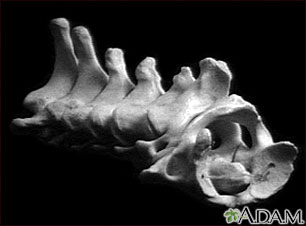

Vertebra, cervical (neck)

Vertebra, cervical (neck)

These are the seven bones of the neck, called the cervical vertebra. The top bone, seen on the right of this picture, is called the atlas, and is where the head attaches to the neck. The second bone is called the axis, upon which the head and atlas rotate. The vertebra are numbered from one to seven from the atlas down, and are referred to as C1, C2, C3, etc.